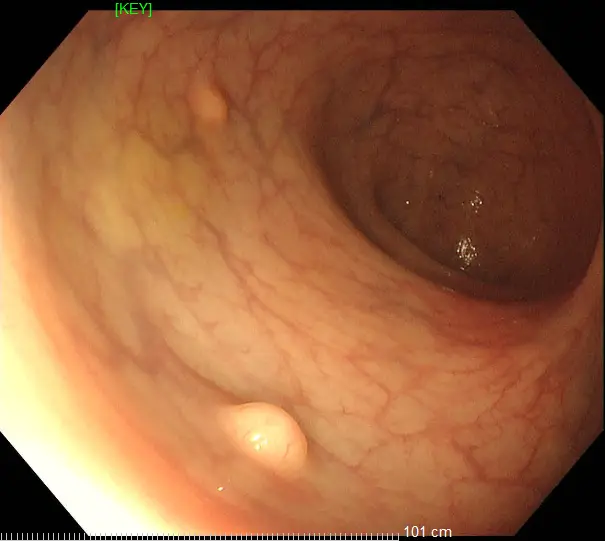

36歲的王先生在蘇州高新區人民醫院行胃腸鏡檢查時,發現直腸裡有1個息肉和2個黏膜下半球型隆起,表面光滑、顏色發黃,大小直徑約1.0cm,當時便做了超聲內鏡檢查,顯示2個隆起的腫物位於直腸黏膜下層,可能是神經內分泌腫瘤,1個粘膜層隆起的息肉可能是腺瘤腫瘤。消化科團隊立即為王先生進行了腸鏡下黏膜剝離術切除了2個粘膜下腫物,同時進行了腸鏡下粘膜切除術解決了1個腺瘤樣息肉,術後病理顯示:2個是神經內分泌瘤NET G1,切緣乾淨。1個管狀腺瘤伴低階別上皮內瘤變(屬於癌前病變),目前王先生恢復良好,已順利出院。